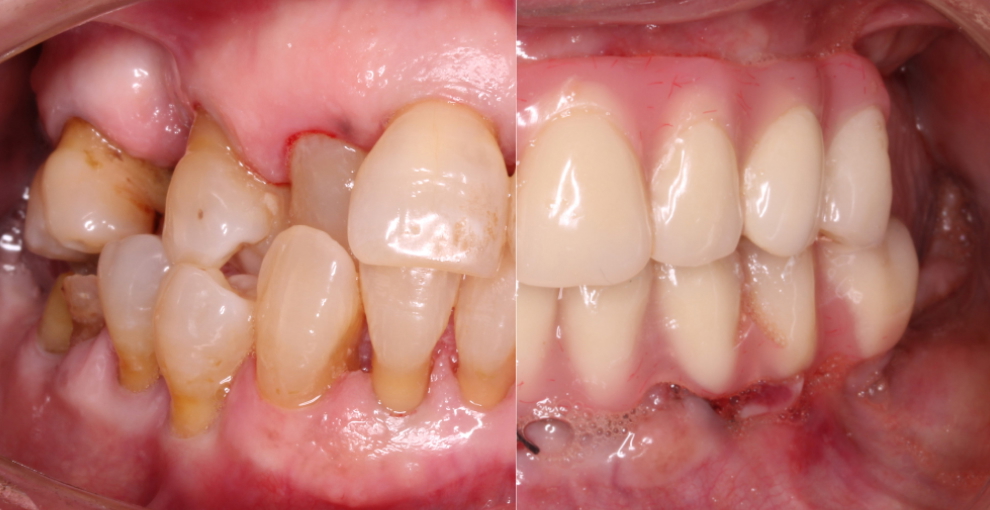

Todo eso, de entrada, lo solucionamos así.

En 5 horas.

Las prótesis son provisionales, pero el cambio real, por el que lloran algunos pacientes, se produce en 5 horas, desde que te sientas en el sillón de la consulta hasta que llegan los dientes provisionales y sales por la puerta.